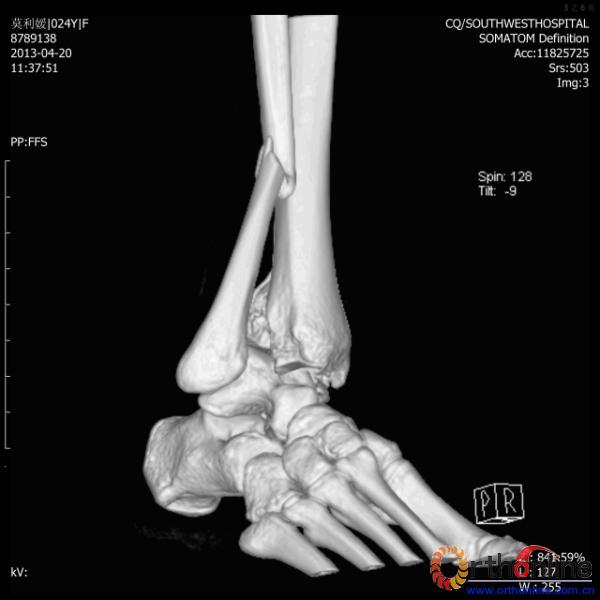

伤员和家属迅速赶到西南医院,10点关节外科段小军副教授查看伤员后急诊收入院,拍摄X片和急诊行三维CT重建检查,提示踝关节创伤严重,出现三踝骨折伴胫距关节脱位,需要急诊手术治疗。随后段教授与正在四川成都参加“汶川地震5周年灾害医学救治研讨会”的杨柳主任联系,进一步完善救治方案。地震当晚,段教授为该伤员进行急诊手术,手术顺利对复杂骨折进行了解剖复位,有效的钢板螺钉固定。术后伤员的疼痛明显缓解,复查X片,踝关节结构恢复满意。

患者术前CT(一)